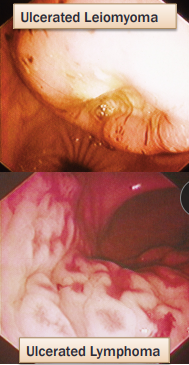

Gastric Neoplasia

Malignant: Adenocarcinoma (dogs), Lymphoma (cats)

Benign: Leiomyoma (dogs), Polyps (cats and dogs)

CS: Chronic vomiting, weight loss, +/- hematemesis; +/- anemia

GI bleeding, delayed gastric emptying, vomiting, anorexia, weight loss

Dx: gastroscopy, biopsy

TX: Surgical resection, chemo(lymphona)

Prognosis: poor w/ malignant

Gastroduodenal Ulcers

Et: NSAID, Steroid, GDV, MCT, renal dz, hepatic dz, sepsis

NSAIDs block PG synthesis → ↓ mucus, bicarb, blood flow → mucosal erosion

NSAID + steroid = ulcer

Cs: Hematemesis, melena, anemia, pale MM

Dt: Endoscopy (#1), regen/ iron-deficiency anemia, ↓ protein, thick mucosa

Determine GI or systemic

Tx: Fluids, (PPI) Omeprazole, Sucralfate